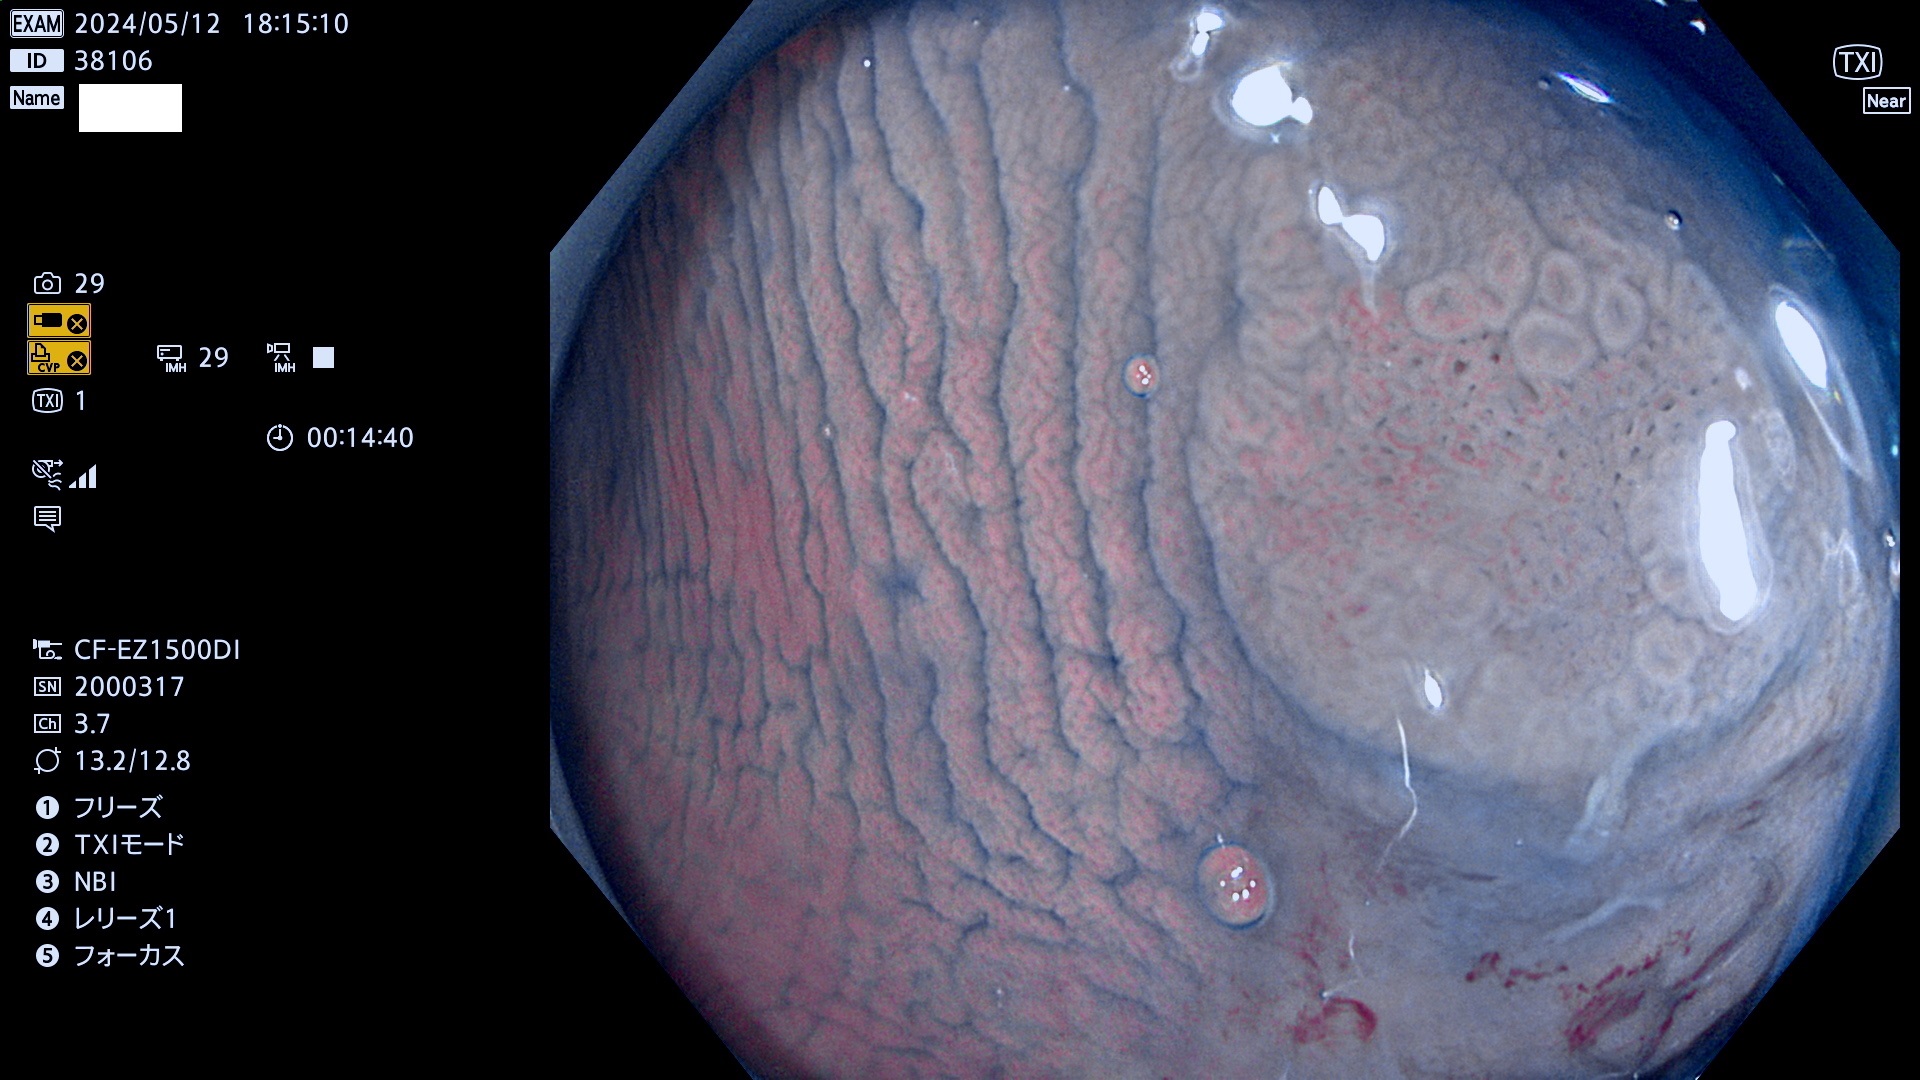

表面型腺腫(Flat Adenoma)の中で、完全に平坦な物をUb、陥凹している物をUcと呼びます。平坦隆起型(Ua)よりも、発見が難しく危険な病変です。

毎週の検査(木・金・土・日)に発見されたUb、Uc型・腺腫を、その週の日曜の夜にUPし1週間、提示します。

抽出の対象期間 2024年5月9日〜5月13の5日間(50件の検査)6件 (6/50=12%)